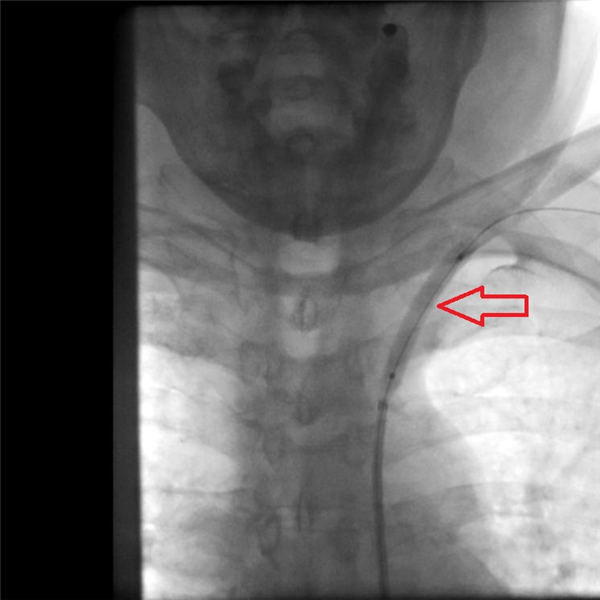

上图红色箭头为张老先生接近闭塞的左侧锁骨下动脉狭窄段。

通过手术中造影显示,左侧锁骨下动脉明显狭窄(下图红色箭头所示部位)。